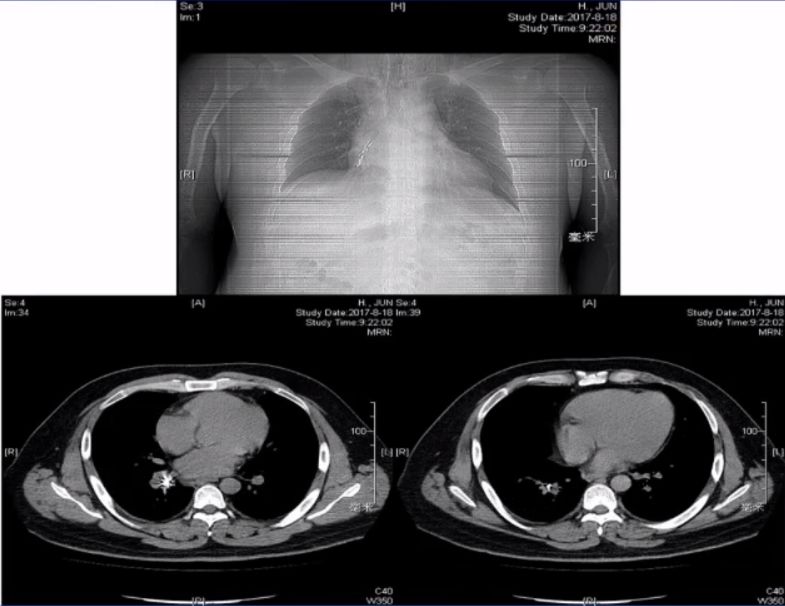

◆胸部CT

-主气管颈段及右肺下叶支气管异物,双侧胸壁、颈部皮下及纵隔内积气,右肺少许炎症

▪胸部CT

-右侧胸腔积液伴肺不张,右主支气管开口见腔内组织影

-纵隔向右移位,左肺少许斑片模糊影